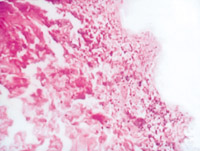

5-2-1 伤后第1天,表皮凝固性坏死,真皮浅层胶原纤维变性 HE×100